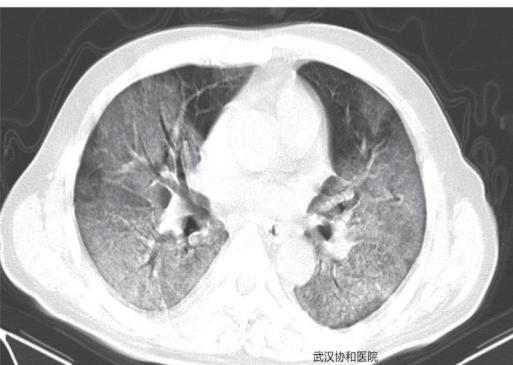

在最新发布的中疾控周报中,中国疾病预防控制中心主任高福表示,展望未来,2021年依旧有许多不确定因素,其中之一就是新冠肺炎或将成为全球或局部地区长期流行的传染性疾病。此外,新冠肺炎的许多新特征被陆续报出,比如被感染的患者可能将面对长期的后遗症、反复感染、复阳以及长期或间歇性的潜伏期等。